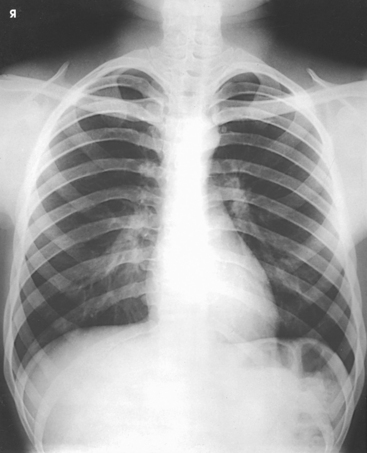

The 12 pairs of ribs are numbered consecutively from superiorly to inferiorly (Fig. 9-4; see Figs. 9-1 and 9-2). The rib number corresponds to the thoracic vertebra to which it attaches. Each rib is a long, narrow, curved bone with an anteriorly attached piece of hyaline cartilage, the costal cartilage. The costal cartilages of the first through seventh ribs attach directly to the sternum. The costal cartilages of the 8th through 10th ribs attach to the costal cartilage of the 7th rib. The ribs are situated in an oblique plane slanting anteriorly and inferiorly so that their anterior ends lie 3 to 5 inches (7.6 to 12.5 cm) below the level of their vertebral ends. The degree of obliquity gradually increases from the 1st to the 9th rib and then decreases to the 12th rib. The first seven ribs are called true ribs because they attach directly to the sternum. Ribs 8 to 12 are called false ribs because they do not attach directly to the sternum. The last two ribs (11th and 12th ribs) are often called floating ribs because they are attached only to the vertebrae. The spaces between the ribs are referred to as the intercostal spaces.

The ribs located above the diaphragm are best examined radiographically through the air-filled lungs, whereas the ribs situated below the diaphragm must be examined through the upper abdomen. Because of the difference in penetration required for the two regions, the position and respiratory excursion of the diaphragm play a large role in radiography of the ribs.

The position of the diaphragm varies with body habitus: It is at a higher level in hypersthenic patients and at a lower level in asthenic patients (Fig. 9-9). In sthenic patients of average size and shape, the right side of the diaphragm arches posteriorly from the level of about the 6th or 7th costal cartilage to the level of the 9th or 10th thoracic vertebra when the body is in the upright position. The left side of the diaphragm lies at a slightly lower level. Because of the oblique location of the ribs and the diaphragm, several pairs of ribs appear on radiographs to lie partly above and partly below the diaphragm.